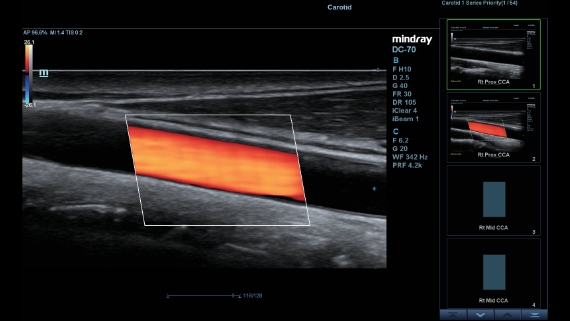

X-Insight, daha geli?mi? g?rĂŒntĂŒler elde etmek i?in kapsaml? bir ??zĂŒmdĂŒr.

Mindrayâin yeni ??zĂŒmĂŒ, geli?en en yeni ultrason teknolojileri ile birlikte, mĂŒ?terilerin g?rĂŒ?lerini klinik gerekliliklerle tam anlam?yla birle?tiren bir ??zĂŒmdĂŒr. Taptaze bir ruhla, gelece?e odaklanarak ve s?n?rs?zl???n pe?inde ko?arak, artan ?l?eklenebilirlikte sĂŒrekli olarak geli?en bir ??zĂŒmdĂŒr.

?ok y?nlĂŒ bir partner olarak, X-Insight'l? DC-60 Exp, her y?nĂŒyle gĂŒnlĂŒk klinik uygulamay? kolayl?kla ve belirsizlik olmadan y?netmenize yard?mc? olacak kapsaml? bir ??zĂŒm sunar.

MĂŒ?teri gereksinimlerine y?nelik g?rĂŒ?ler temelinde, X-Insight'l? DC-60 Exp, eXpress Clarity, eXceptional Intelligence ve eXceeding Experience ile gĂŒ?lendirilerek, hassas g?rĂŒntĂŒlemeyle yĂŒksek verimlilik sa?layacak ?ekilde tasarlanm??t?r.